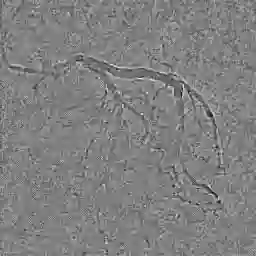

The adoption of machine learning in healthcare calls for model transparency and explainability. In this work, we introduce Signature Activation, a saliency method that generates holistic and class-agnostic explanations for Convolutional Neural Network (CNN) outputs. Our method exploits the fact that certain kinds of medical images, such as angiograms, have clear foreground and background objects. We give theoretical explanation to justify our methods. We show the potential use of our method in clinical settings through evaluating its efficacy for aiding the detection of lesions in coronary angiograms.